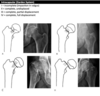

Intracapsular (Garden classification)

Intracapsular NOF fracture Garden classification type I

Intracapsular NOF fracture Garden classification type II

Intracapsular NOF fracture Garden classification type III

Intracapsular NOF fracture Garden classification type IV

Extracapsular (intertrochanteric) fracture

Extracapsular (subtrochanteric) fracture

Extracapsular NOF